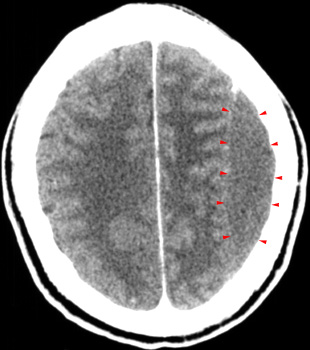

Subacute

SDH may be difficult to visualize by CT because as the hemorrhage is reabsorbed

it becomes isodense to normal gray matter. A subacute SDH should be suspected

when you identify shift of midline structures without an obvious mass.

Giving contrast may help in difficult cases because the interface between

the hematoma and the adjacent brain usually becomes more obvious due to

enhancement of the dura and adjacent vascular structures. Some of the

notable characteristics of subacute SDH are:

- Compressed lateral ventricle

- Effaced sulci

- White matter "buckling"

- Thick cortical "mantle"